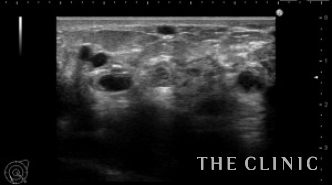

エコーでは多数のヒアルロン酸のしこりを認め、皮膚の発赤部分の深部は炎症のため診断できませんでした。

ヒアルロン酸注入によるしこりのエコー診断カルテ